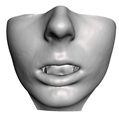

2.6. Textured Output Visualization